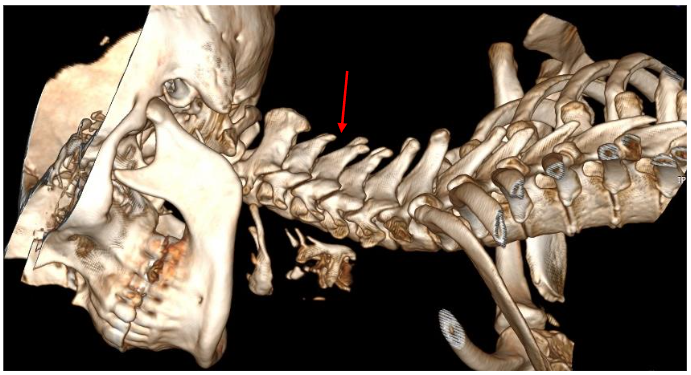

This case report describes a patient with chronic neck pain following cervical spine manipulation techniques. The patient presented with significant neurological symptoms on both sides of the neck, caused by combined end-range cervical rotation and extension. We decided not to proceed with axial MRI in these cases. We followed up with an axial view, which showed…

This study outlines a standardized protocol for magnetic resonance imaging (MRI) of the cervical spine using the 3T Siemens Skyra/Numaris4, Version Syngo MR E11. Utilizing a 20-channel Head and Neck coil, the imaging focuses on evaluating ligament integrity, particularly the atlas C1, through a combination of neutral and rotated positions.

Case Report Findings

We positioned the cervical spine in a rotated position, and the findings showed that the C1-2 segment placed under tension. The MRI results indicated a cross-sectional lesion to the Anterior Longitudinal Ligament illustrated in Figure 10.